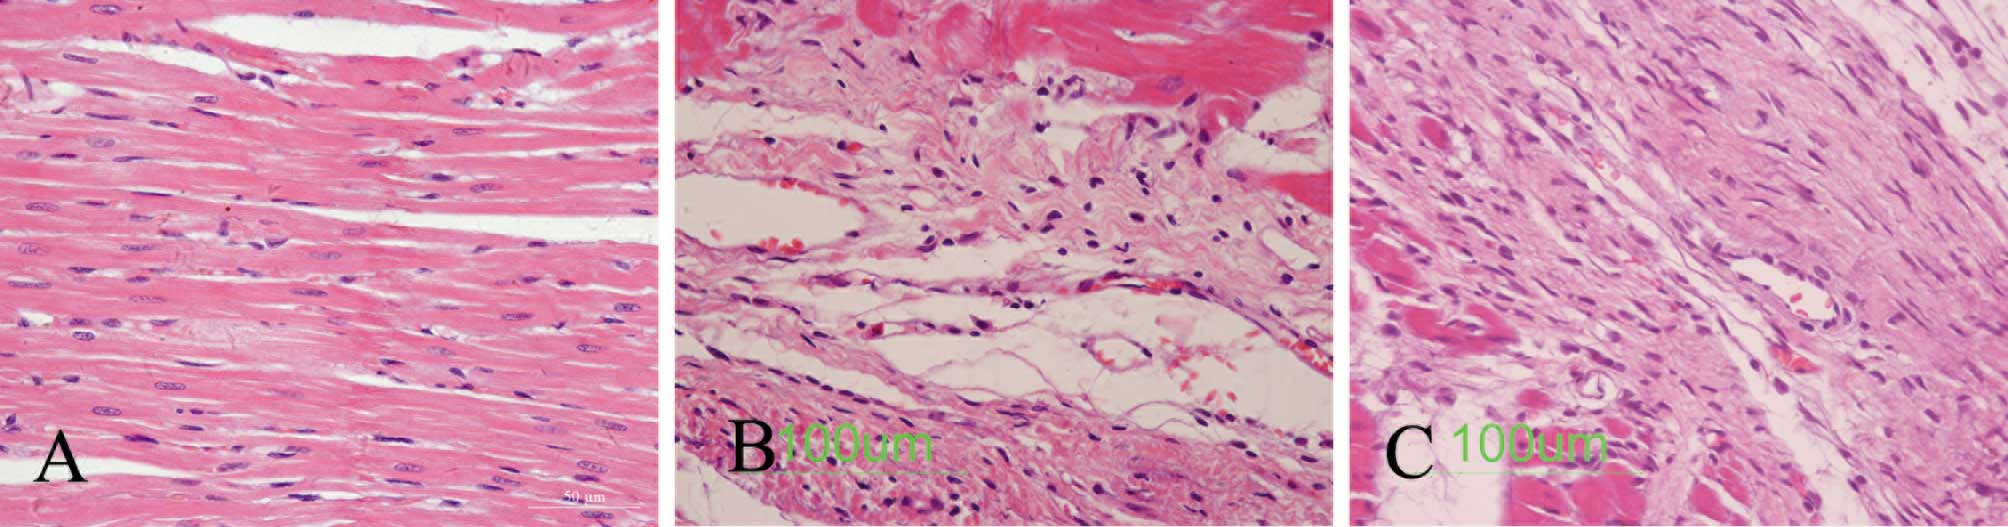

As shown in Fig. 2B, infarction, myocardial fibrosis, the collagen deposition area and the remnants of cardiac disorder were substantially severe in the myocardial infarction group rats. Fig. 2C demonstrates a notably higher number of small vessels around the infarcted myocardium in the EPO treatment group rats than in the myocardial infarction group rats. The myocardial interstitial fibrosis area was also improved in the EPO treatment group rats (Fig. 2).

Figure 2.

Pathological changes in the myocardium of (A) a control rat, (B) a myocardial infarction rat and (C) an EPO treatment rat 4 weeks after operation by H&E staining.